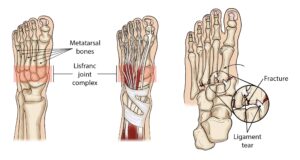

The midfoot, located in the central region of the foot, consists of a cluster of small bones that form the arch visible on the top of the foot. From this cluster, five long bones, known as metatarsals, extend outward to connect with the toes. These bones are stabilized by robust ligaments forming the Lisfranc joint complex, which secures the bones both across and along the foot. Notably, there is no ligament connecting the first and second metatarsals, making this area vulnerable to injury during twisting falls, which can result in fractures or dislocations. The Lisfranc joint complex plays a crucial role in foot stability and function, as it permits minimal movement while providing critical support to the arch. This stability is essential for the effective transfer of force during walking, as the midfoot channels the power generated by the calf muscles toward the front of the foot. When a Lisfranc injury is not properly treated, it can lead to persistent instability in the arch, potentially causing it to collapse or flatten, which may significantly impair walking and overall foot function

The Lisfranc joint complex includes the bones and ligaments that connect the midfoot and forefoot. Lisfranc injuries include ligament strains and tears, as well as fractures and dislocations of bone (far right).